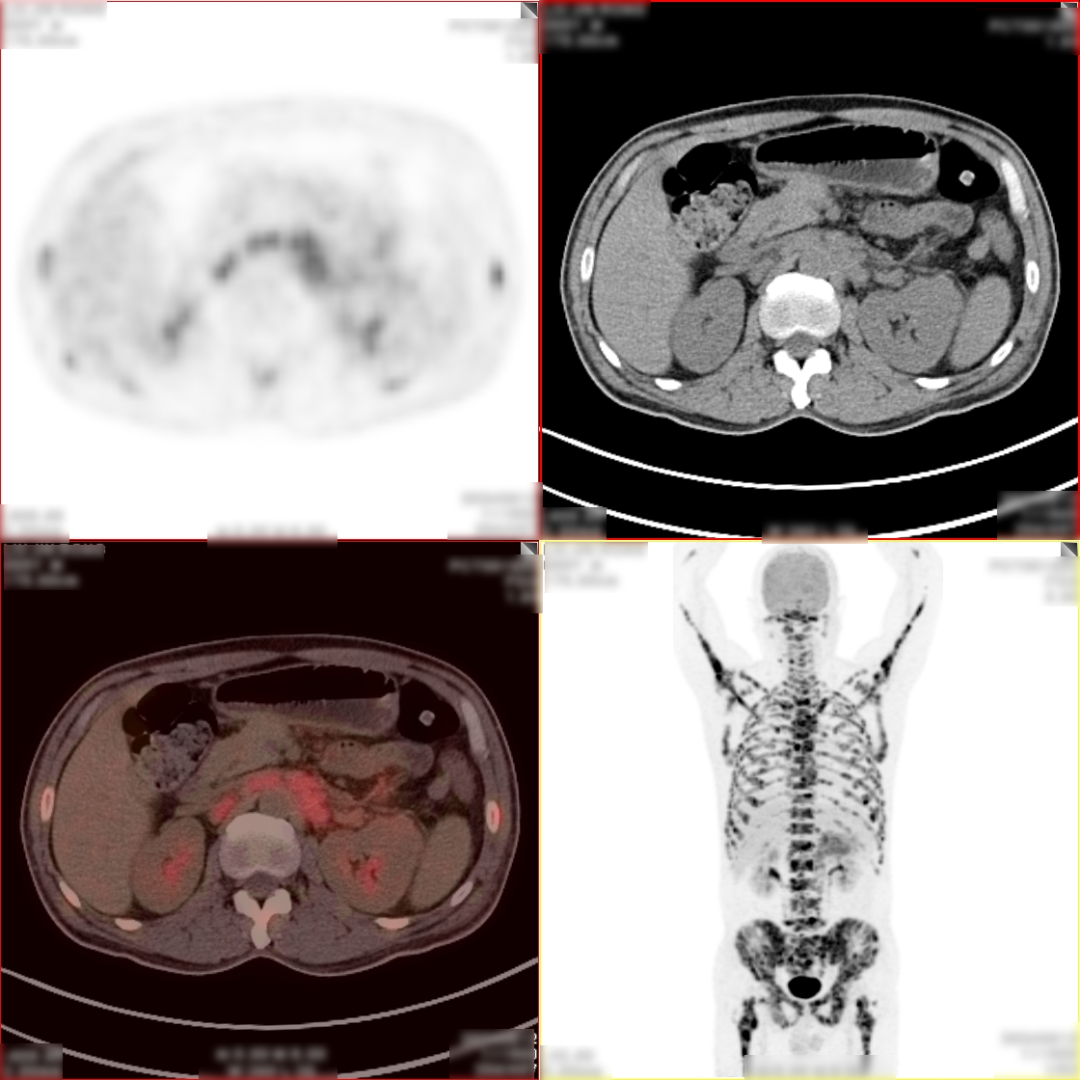

病史:男,55岁,腹痛伴乏力3天入院检查,MR:胰尾部肿物,考虑胰腺癌并多发淋巴结转移;超声胃镜下胰腺活检未见癌细胞,为了解全身状况申请PET检查。

PET/CT检查所见

空腹 6h 以上,静脉注射显像剂 18F-FDG,平静休息 60min 后行全身 PET 及 CT 断 层显像,解剖与功能图像行多层面、多幅显示,影像清晰。

PET/CT诊断意见:

1、胰腺体尾部块状胰腺癌,病灶侵犯相邻胃体部胃壁,并可能侵犯左侧肾周筋膜,肿块远端胰尾部胰管扩张;盆腔少量积液;

2、胰腺尾部周围、中上腹部腹膜后区腹主动脉周围及纵隔内(1R、1L、2R、4R、5、7 组)多发淋巴结转移灶;